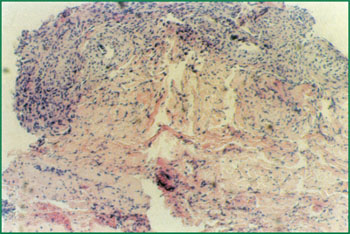

1、 Ⅲ度燒傷占總面積85%的病人,右側(cè)為皮膚全層壞死(病理切片)。

4、 燒傷壞死皮膚液化排除創(chuàng)面形成纖維隔離膜,新生的皮膚組織再生復(fù)原創(chuàng)面(病理切片),(傷后第20天)。

6、 病理切片:原位干細(xì)胞再生復(fù)原皮膚。

8、 已愈合的皮膚組織切片,可見已形成正常的皮膚組織結(jié)構(gòu)。(傷后49天)。